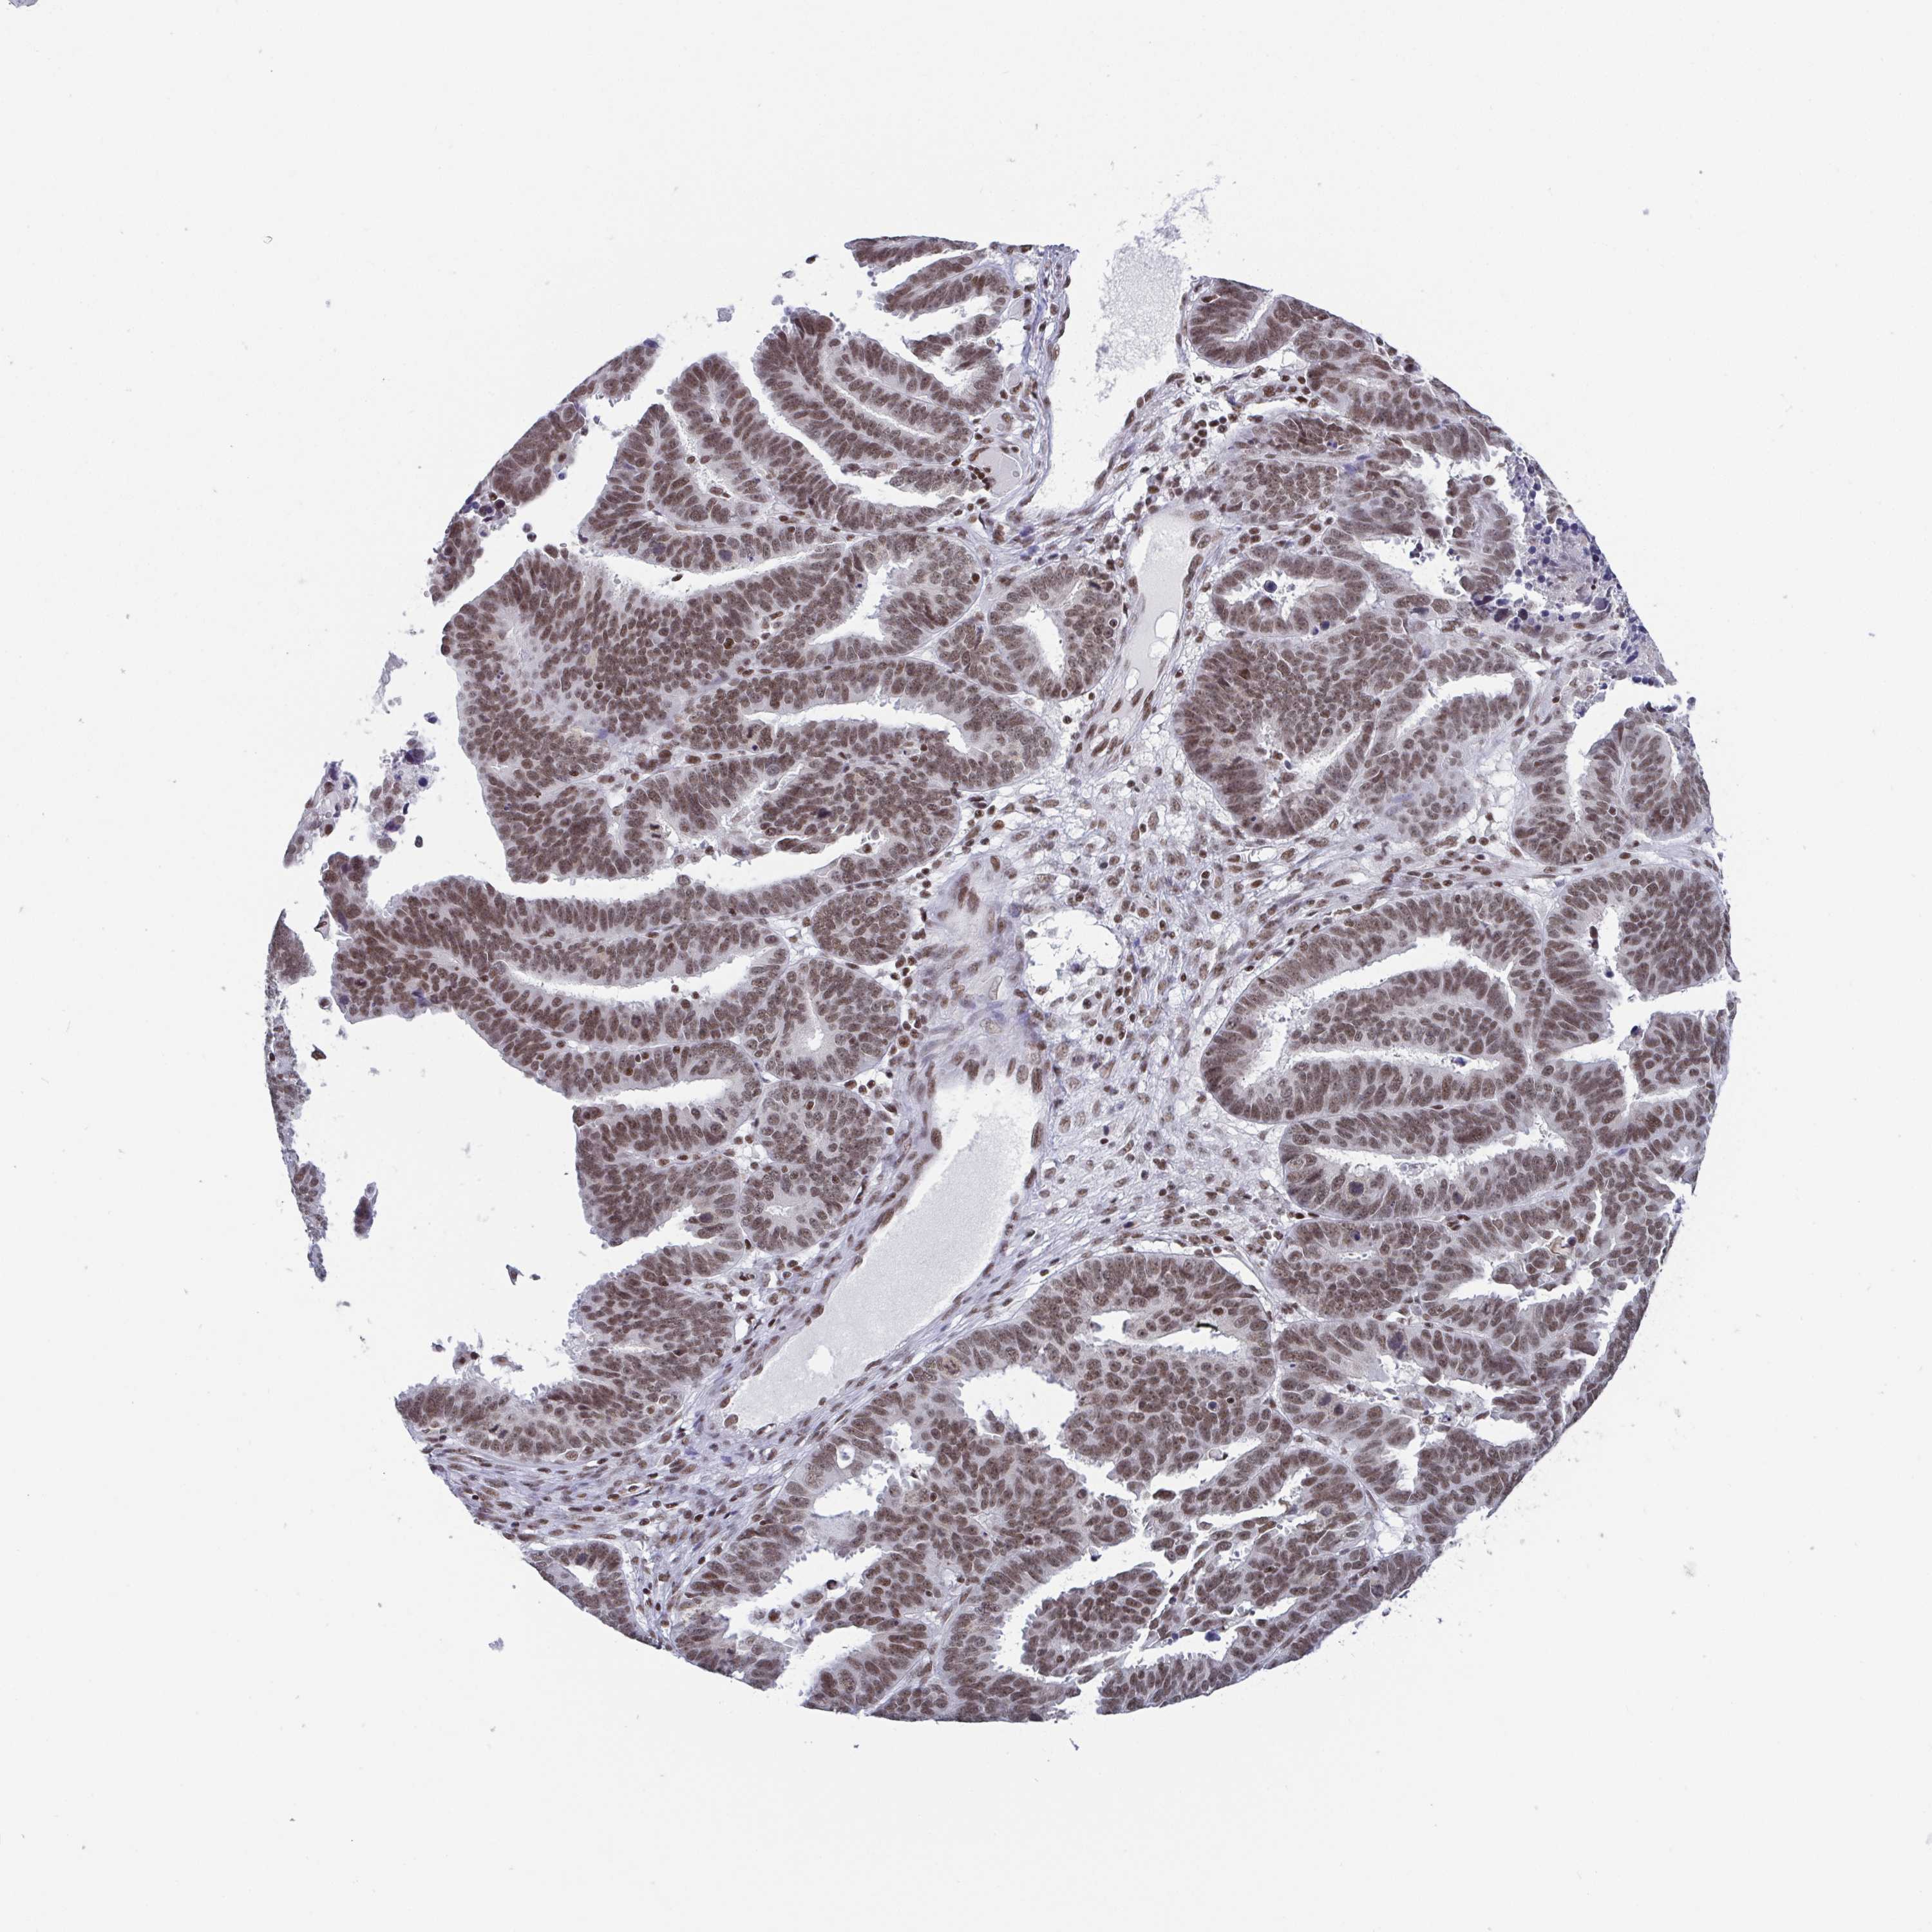

OVARIAN CANCER - Protein expressioni

A mouse-over function shows sample information and annotation data. Click on an image to view it in a full screen mode. Samples can be filtered based on level of antibody staining by selecting one or several of the following categories: high, medium, low and not detected. The assay and annotation is described here.

Note that samples used for immunohistochemistry by the Human Protein Atlas do not correspond to samples in the TCGA dataset.

Antibody stainingi

Antibody staining in the annotated cell types in the current human tissue is reported as not detected, low, medium, or high, based on conventional immunohistochemistry profiling in selected tissues. This score is based on the combination of the staining intensity and fraction of stained cells.

Each image is clickable and will lead to virtual microscopy that enables deeper exploration of all samples and also displays staining intensity scores, fraction scores and subcellular localization as well as patient and tissue information for each sample.

Antibody HPA004122

Antibody CAB062550

Antibody CAB068181

Antibody CAB068182

Cystadenocarcinoma, serous, NOS

Cystadenocarcinoma, mucinous, NOS

Carcinoma, endometroid

Carcinoma, NOS

Adenocarcinoma, NOS